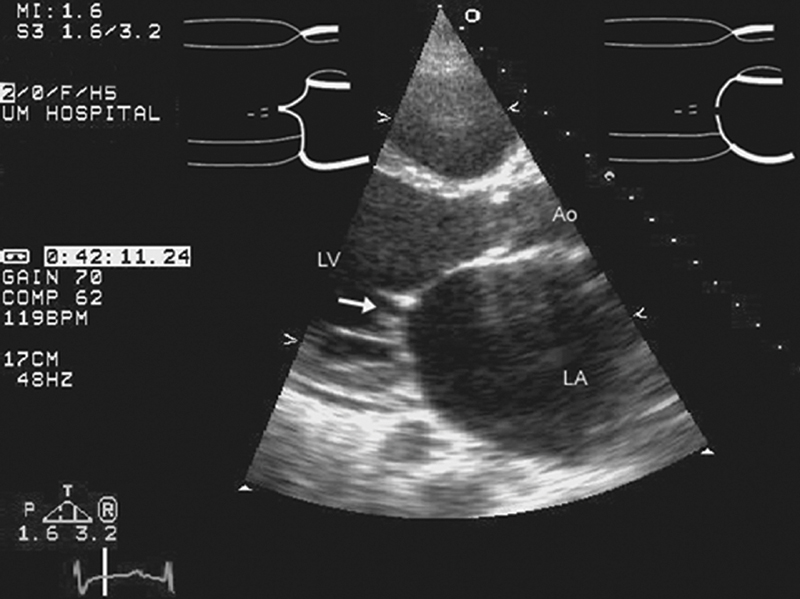

فحوصات تشخيصية لبعض امراض القلب والشرايين التاجية